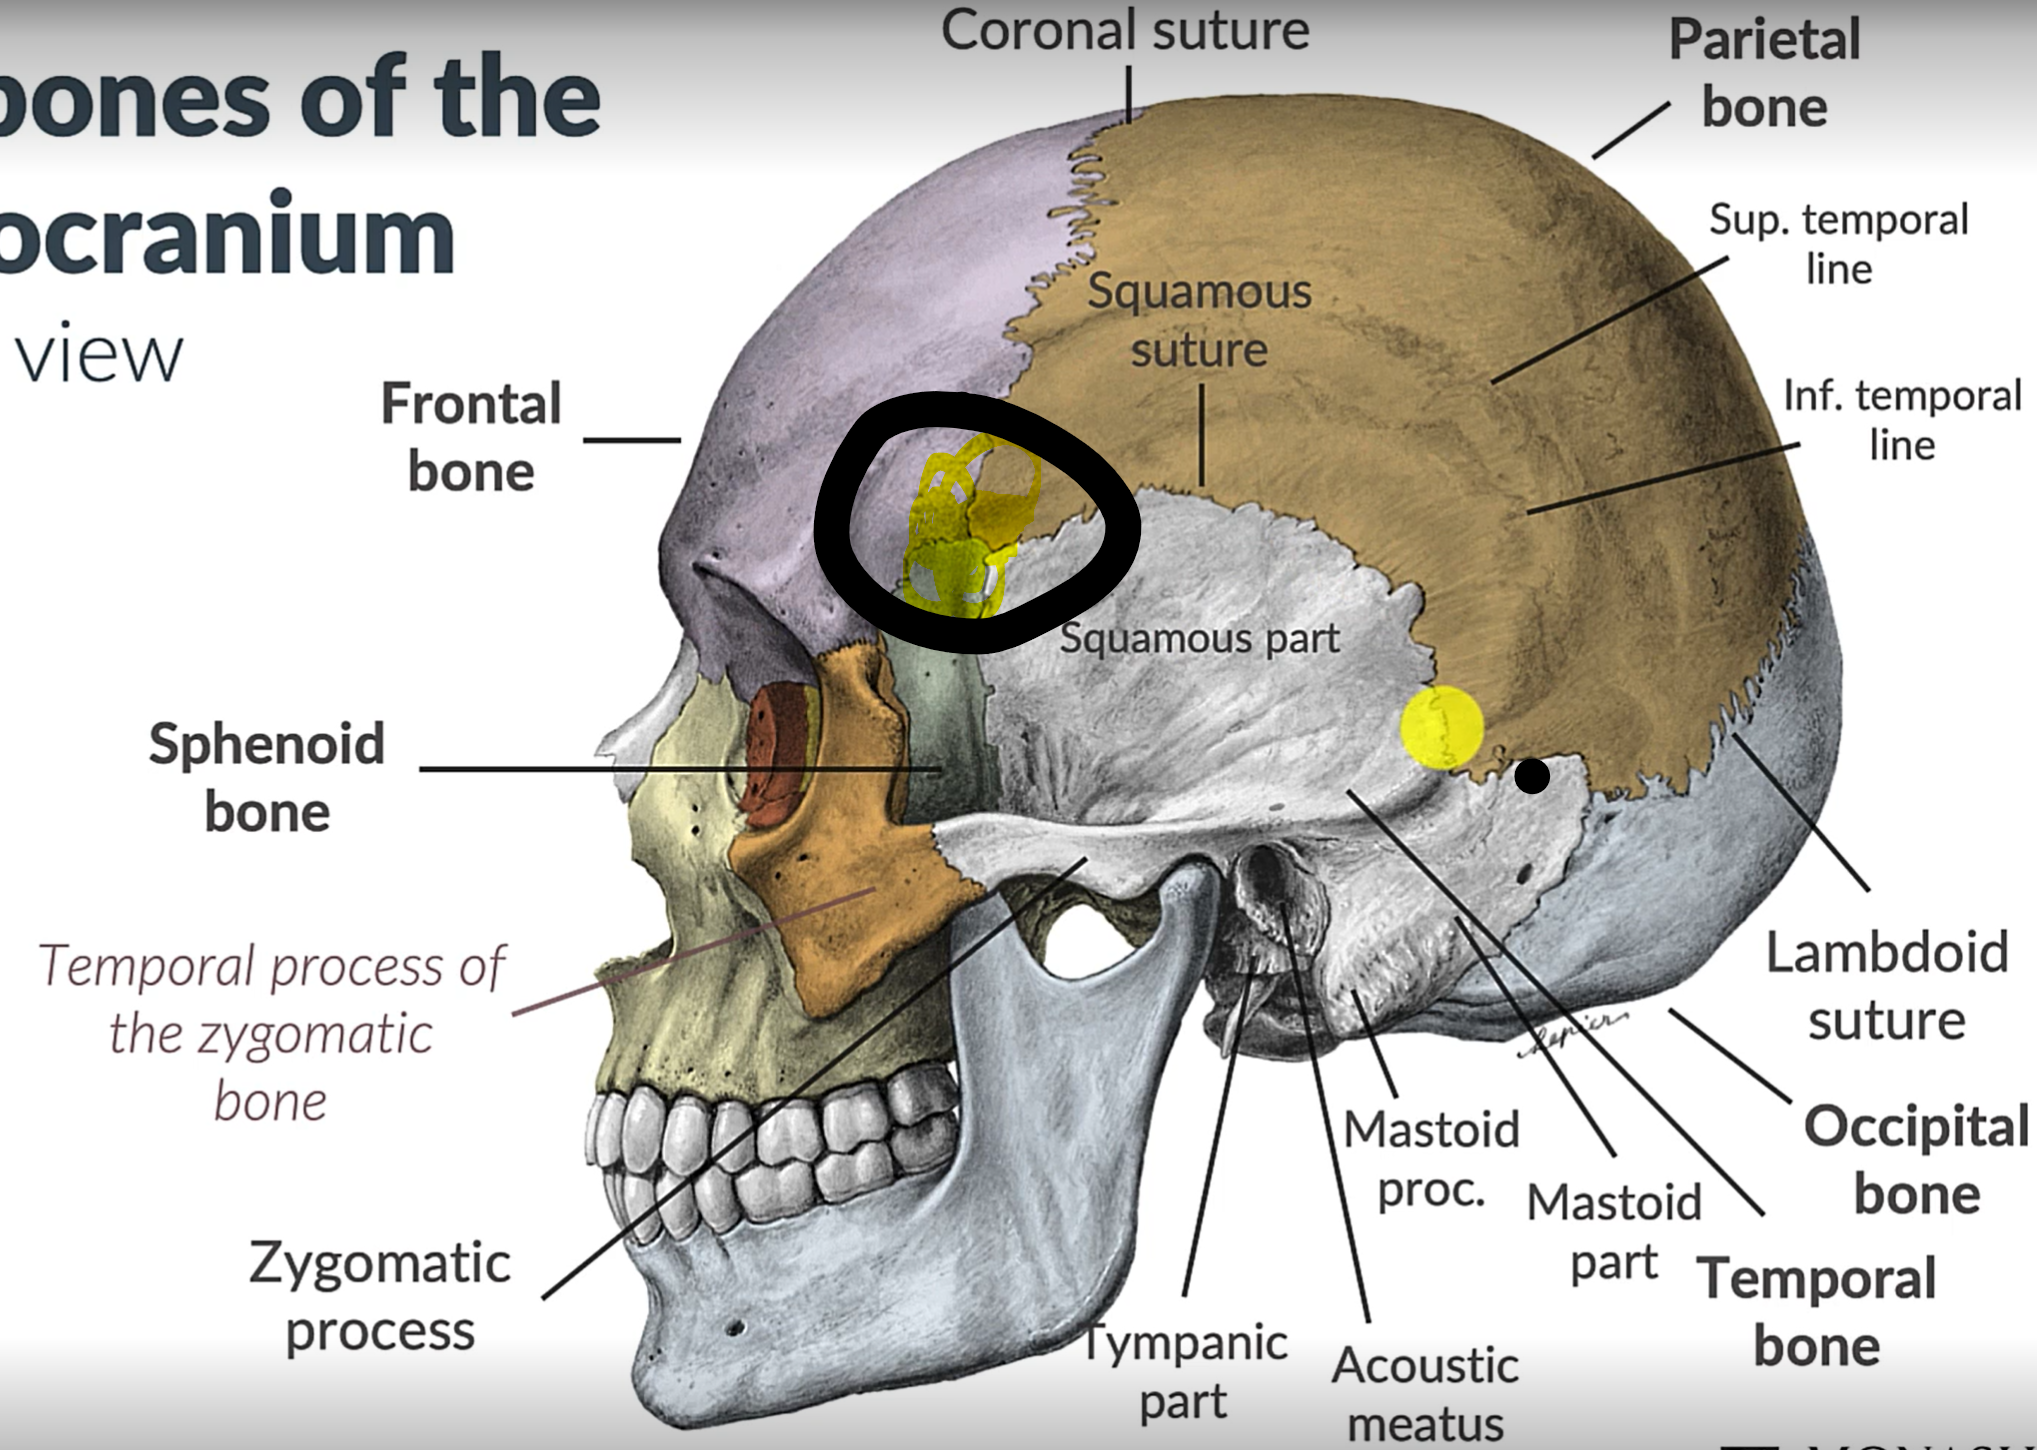

What is the pterion?

The point where the frontal, parietal, sphenoid and temporal bones meet.

Pterion